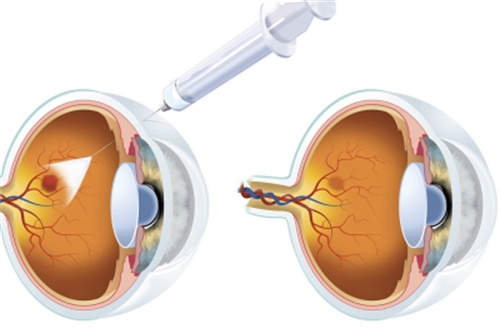

对于黄斑病变患者,她能熟练进行抗VEGF药物注射治疗,有效控制病情发展。

眼内注药术:治疗黄斑水肿、新生血管等